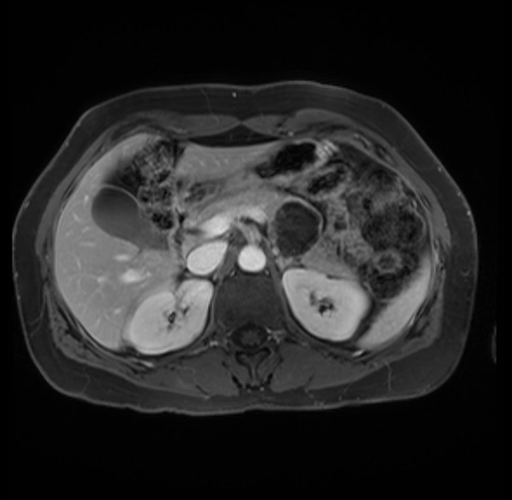

Imaging Analysis

Look through the patient's CT scan to identify any areas of concern for the necessary procedure.

Based on your CT findings, which issue(s) are present and would give reason for "planned slowing down moment(s)" in this case?

Considering a standard distal pancreatectomy procedure, what step(s) of the operation would you do differently in this case?